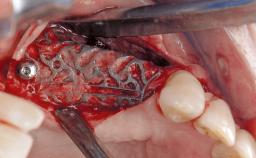

Late Presentation of Peri-Implant Mucositis Requiring Soft-Tissue Augmentation and Esthetic Crown Lengthening at Implant Site 11

Biological or technical complications around implant-supported prostheses place a significant burden on patients as well as the surgical and restorative team. Inflammation of the peri-implant soft tissues is often the first sign that something has gone awry. While there is never a good time for a complication, late presentation of inflammation in the soft tissues around a long-standing prosthesis triggers a period of research and review of the case in order to ascertain the treatment history and its possible contribution to the etiology of the situation. This becomes more complicated in situations where a patient has not received regular maintenance and clinical/radiographical examinations due to personal, financial, or professional reasons. When the complication occurs in the esthetic zone, the complexity of the situation expands exponentially, as the only acceptable outcome in the patient’s eyes will be the maintenance of the esthetics of the prosthesis.